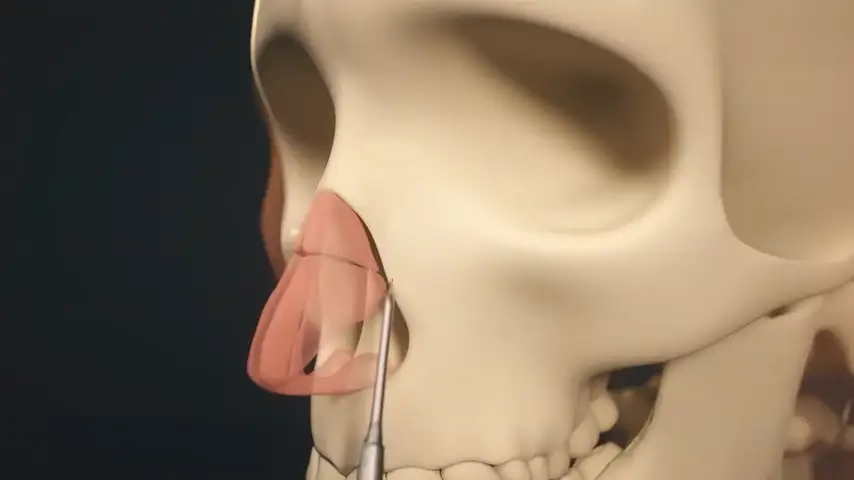

Lateral osteotomy of nasal bone

Transverse osteotomy of nasal bone

Drilling of septum for suture fixation

Details

The finest and angled insert for insertion in limited space;

ideal for perforating nasal bones as well as ethmoid lamina splints.

Recommended insert:

Advantages over traditional tools

Reduced risk of damaging anatomically complex regions

Greater intraoperative control and bone management

Micrometric cut for minimal bone loss

Reduced heat generation to avoid bone necrosis